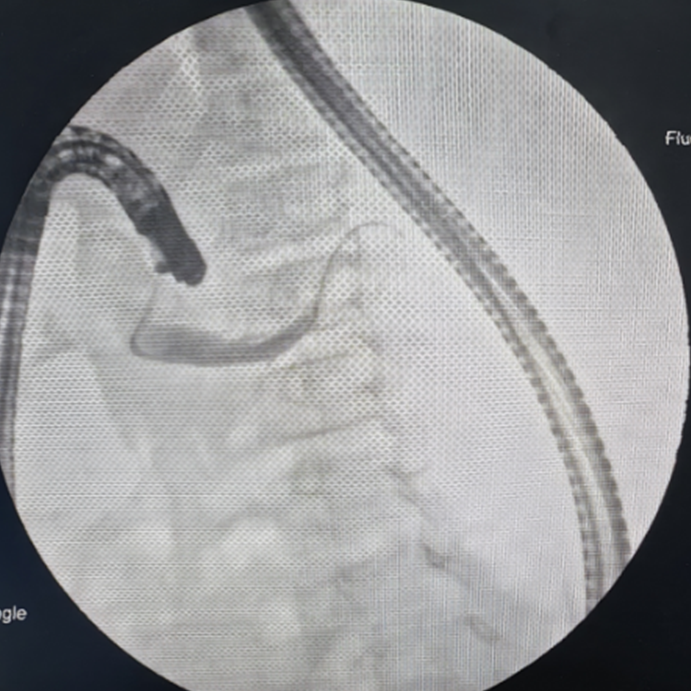

巴桑卓玛副主任医师为一例11岁的胰腺分裂症患儿完成经副乳头插管的ERCP检查及胰管内支架置入术。